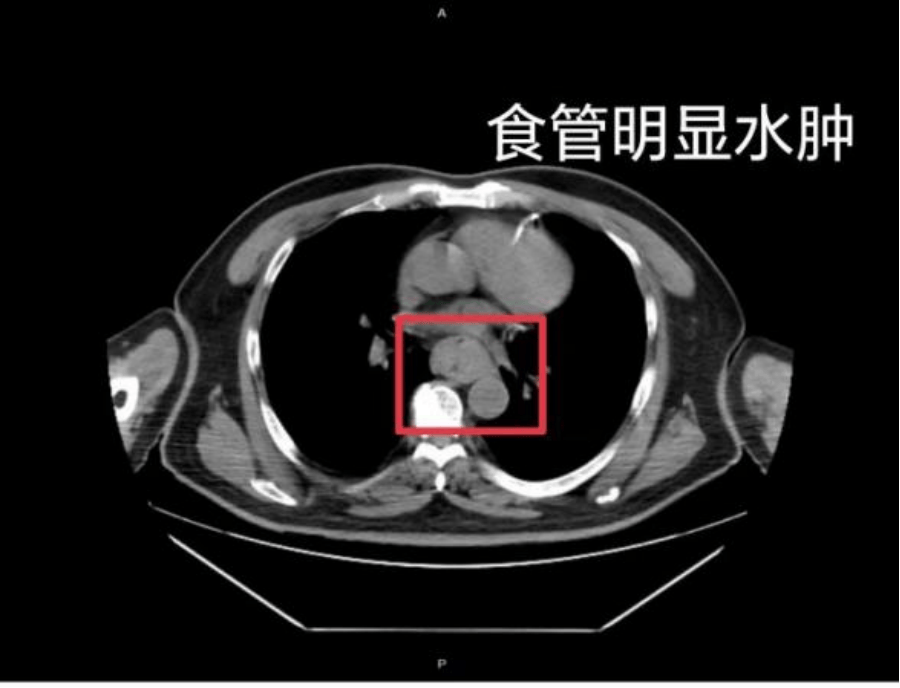

这样的情况并非个例,同样在近日,福州一位网友分享了自己因吃了一碗很烫的福鼎肉片导致呕血,并查出食管水肿的经历虚拟币天王。

据网友回忆,“自己去厕所尝试呕吐时,直接呕出了血,一大口鲜血从嘴里喷出,总共吐了两次虚拟币天王。”CT 结果显示,他的食管全部出现水肿损伤。